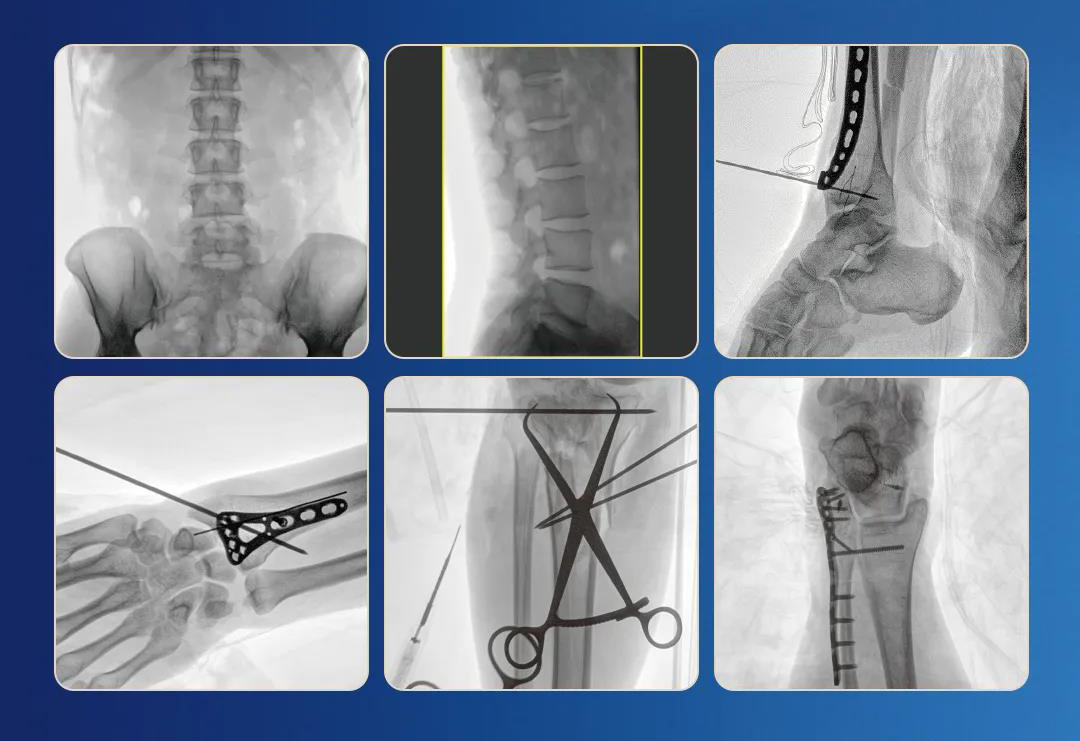

一、臨床應用

1.關節手術

2.創傷手術

3.脊柱手術

4.疼痛治療

采用30cmx30cm大尺寸動態平板探測器,成像面積較傳統平板探測器大幅提升。

清晰的像素,低信噪比,細小的組織結構也可以清晰顯示。